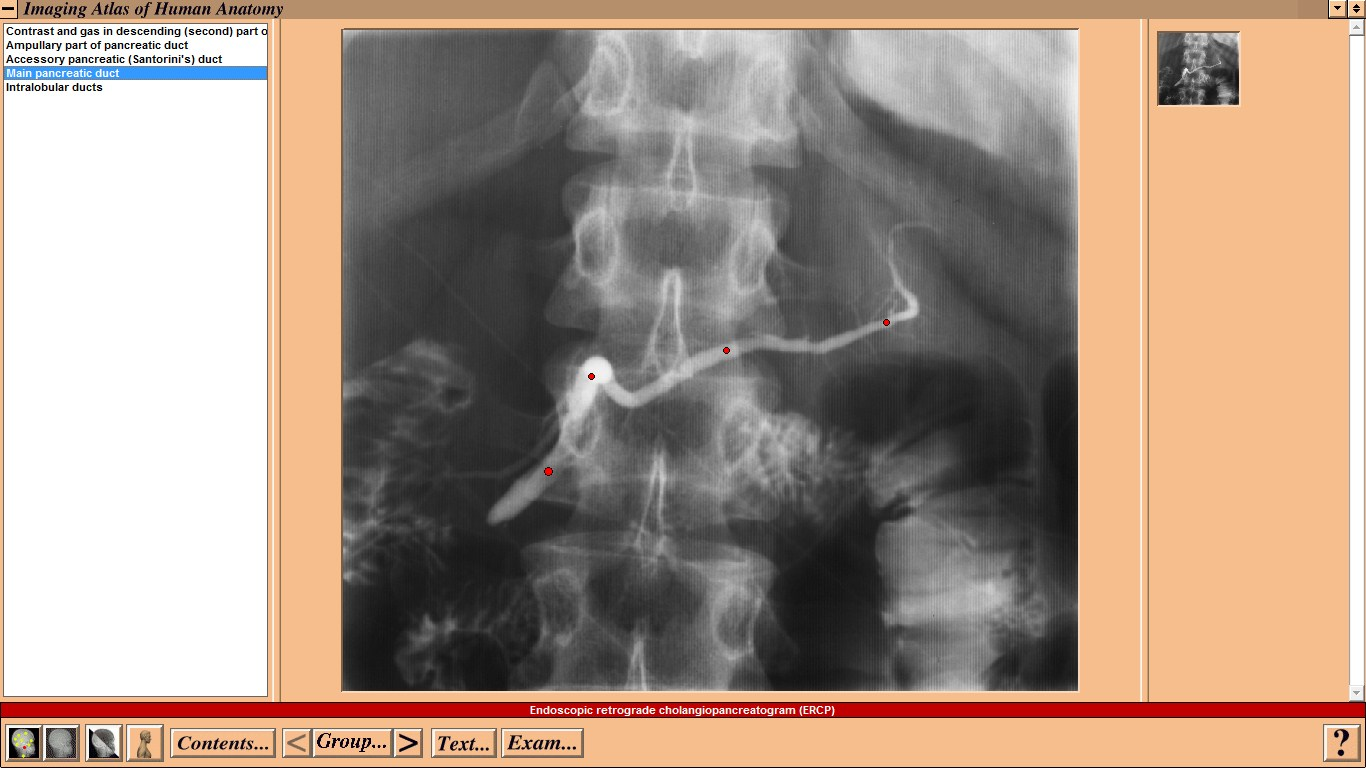

Mosby - Imaging Atlas of Human Anatomy by Jamie Weir and Peter H. Abrahams - CD-ROM

Mosby - Imaging Atlas of Human Anatomy by Jamie Weir and Peter H. Abrahams - CD-ROM Год выпуска: 1995 Версия: 1.0 Разработчик: Mosby Платформа: WindowsСовместимость с Vista: неизвестно Системные требования: IBM or compatible PC, 486SX, 8MB RAM, 640 × 480 display, 256 colors, double speed CD-ROM drive, Microsoft Windows 3.1 or later, optimum: Pentium processor, 800 × 600 display, more than 256 colors, ISBN 0-7234-2187-0, St Louis, Mo, Mosby, 1995 Язык интерфейса: только английский Таблэтка: Не требуется Описание: This CD-ROM provides a detailed atlas of radiologic anatomy in all forms, including plain films, magnetic resonance (MR) imaging, computed tomography (CT), venography, and angiography. It is formatted to present a concise atlas, cephalad (skull) to caudad (feet). The disc is easy to work with, and I did not have any trouble setting it up. The graphics and table of contents are laid out well. Navigating the various parts is relatively simple. The opening graphics are well displayed, allowing instant access to pictures or the table of contents; therein lies the simplicity of finding an anatomical part of the body to review. Each screen contains a picture of the radiograph accessed, key landmarks (with a glossary that can be turned off), related slides that can easily be accessed, and a self-exam. Диск содержит более чем 3500 радиографических изображений нормальной анатомии, включая обычные рентгенограммы, КТ, МРТ, ангиограммы, артериограммы и видео УЗИ. Исчерпывающий уровень анатомических ориентиров с возможностью самоконтроля. Издание рассчитано прежде всего на рентгенологов. Доп. информация: Поскольку издание старое, придется установить древнюю версию Quick Time - 2.0.3.51 (есть на самом диске).   Набор в группу «Хранители» - Помогите сохранить редкие раздачи Mosby - Imaging Atlas of Human Anatomy by Jamie Weir and Peter H. Abrahams - CD-ROM Год выпуска: 1995 Версия: 1.0 Разработчик: Mosby Платформа: Windows Совместимость с Vista: неизвестно Системные требования: IBM or compatible PC, 486SX, 8MB RAM, 640 × 480 display, 256 colors, double speed CD-ROM drive, Microsoft Windows 3.1 or later, optimum: Pentium processor, 800 × 600 display, more than 256 colors, ISBN 0-7234-2187-0, St Louis, Mo, Mosby, 1995 Язык интерфейса: только английский Таблэтка: Не требуется Описание: This CD-ROM provides a detailed atlas of radiologic anatomy in all forms, including plain films, magnetic resonance (MR) imaging, computed tomography (CT), venography, and angiography. It is formatted to present a concise atlas, cephalad (skull) to caudad (feet). The disc is easy to work with, and I did not have any trouble setting it up. The graphics and table of contents are laid out well. Navigating the various parts is relatively simple. The opening graphics are well displayed, allowing instant access to pictures or the table of contents; therein lies the simplicity of finding an anatomical part of the body to review. Each screen contains a picture of the radiograph accessed, key landmarks (with a glossary that can be turned off), related slides that can easily be accessed, and a self-exam. Диск содержит более чем 3500 радиографических изображений нормальной анатомии, включая обычные рентгенограммы, КТ, МРТ, ангиограммы, артериограммы и видео УЗИ. Исчерпывающий уровень анатомических ориентиров с возможностью самоконтроля. Издание рассчитано прежде всего на рентгенологов. Доп. информация: Поскольку издание старое, придется установить древнюю версию Quick Time - 2.0.3.51 (есть на самом диске).   Набор в группу «Хранители» - Помогите сохранить редкие раздачи Программы и Дизайн » Системы для бизнеса, офиса, научной и проектной работы » Медицина - интерактивный софт